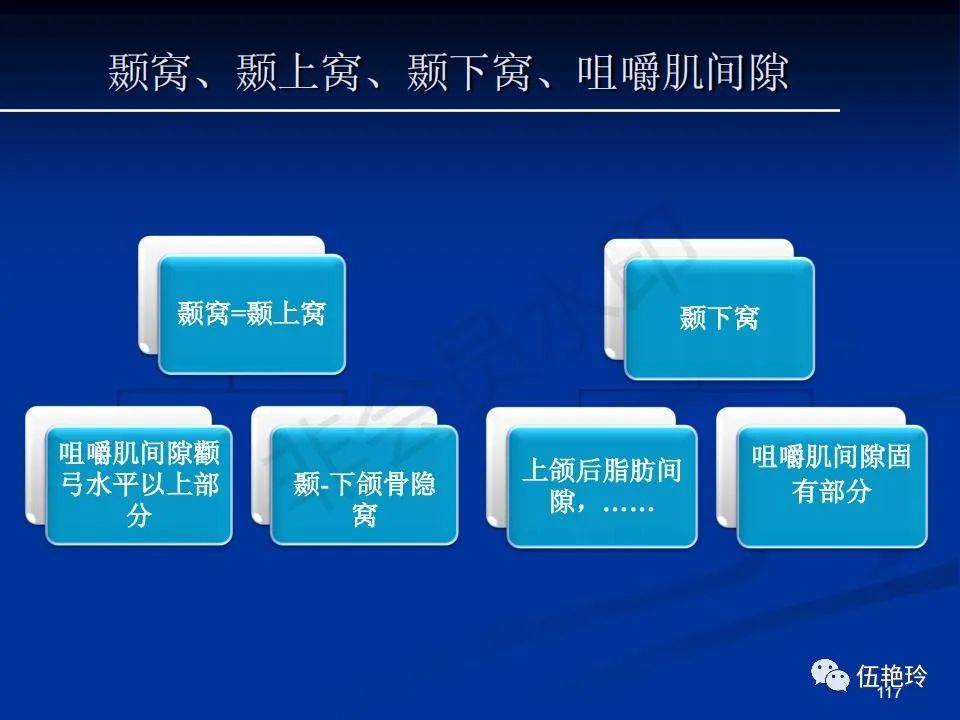

颞下窝与咀嚼肌间隙